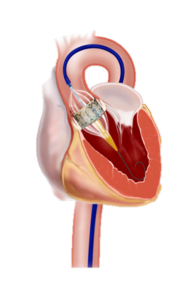

This procedure involves the replacement of the aortic valve to about 70% of the aortic valve via the artery in the groin (transfemoral), about 30% via a small cut on the left side of the thorax through the apex of the heart (transapical). Alternatively, access via a clavicle artery or directly over the aorta can be selected. In all cases, the constricted heart is first distended with a constricted aortic valve (balloon valvuloplasty). Subsequently, a vascular prosthesis with integrated biological heart valve is introduced via a catheter and unfolded at the level of the diseased aortic valve (implantation). The flap anchors itself with a so-called stent in the correct position. This technique is also suitable for new valve implantation in degenerated bioprostheses (valve in valve technique). However, the process has a disadvantage: the calcified heart valves remain in the heart and the lime can dissolve over the years.

Technique of Percutaneous Aortic Valve Implantation: Left Transapical, Right Transfemoral